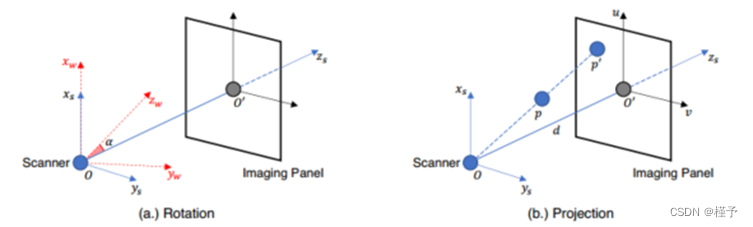

性能。如表1所示,我们在不同输出分辨率的重建设置下比较了DIF-Net与之前的四种方法[1,6,22,29](即,1283、2563)以及来自不同数量的投影视图的投影视图实验表明,我们提出的DIF-Net即使只使用6个投影视图也可以重建具有高图像质量的CBCT,其在PSNR和SSIM值方面明显优于先前的工作。更重要的是,DIF-Net可以直接应用于重建具有不同输出分辨率的CT图像,而不需要模型重新训练或修改。如图3所示的视觉结果,FDK [6]由于缺乏足够的投影视图而产生具有许多条纹伪影的结果; SART [1]和NAF [29]产生具有良好形状轮廓的结果,但缺乏详细的内部信息; FBPConvNet [11]重建了良好的形状和中等的细节,但仍然存在一些条纹伪影;我们提出的DIF-Net可以重建出高质量的CT图像,具有更好的形状轮廓、更清晰的内部信息和更少的伪影。2补充资料中给出了输入视图数量的更直观的比较。

可视化比较。下面的图5显示了不同数量的输入视图的可视化比较。